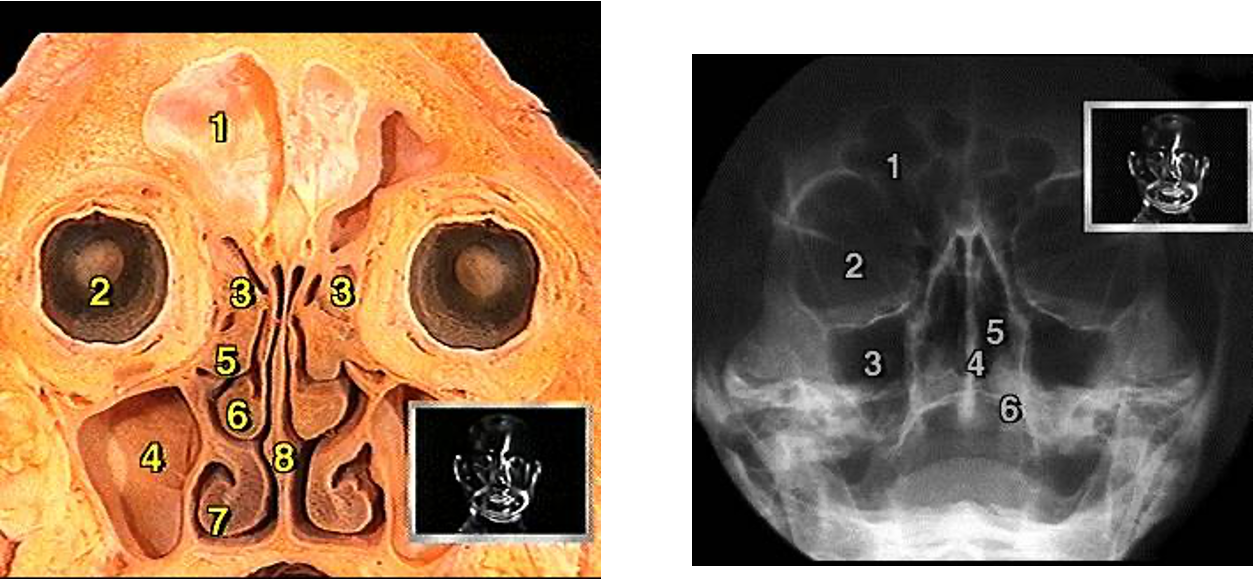

The Maxillary Sinus

- Sinus ostium located in the middle meatus

The Ethmoid Sinuses

- Anterior ethmoids: drain into the middle meatus

- Posterior ethmoids: drain into superior meatus

The Frontal Sinus

The Sphenoid Sinus